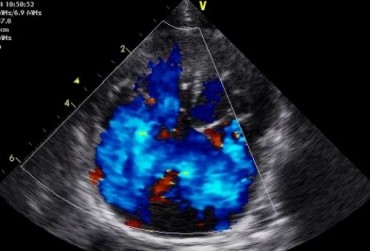

Zwężenie zastawki trójdzielnej jest jedną z form dysplazji pojawiającą się w różnym stopniu nasilenia (najczęściej łącznie z niedomykalnością zastawki) zarówno u psów, jak i u kotów. Cechami charakterystycznymi definiującymi zwężenie zastawki trójdzielnej są: obecność rozkurczowego wybrzuszenia (doming) płatków zastawki, zmniejszona ruchomość płatków, zmniejszona średnica ujścia zastawki. Mimo że zmiany morfologiczne aparatu trójdzielnego są typowe w przebiegu TVD i są znakiem rozpoznawczym tej choroby, nie są one zawsze bardzo silnie wyrażone i nie zawsze można mieć bezsprzeczną pewność diagnostyczną, bazując na badaniu echokardiograficznym [10]. Przypadki takie zdarzają się przede wszystkim u pacjentów, u których nie postawiono diagnozy we wczesnym etapie życia, a którzy pojawiają się na badaniu dopiero w starszym wieku z zaawansowanymi zmianami i niejednokrotnie z klinicznymi objawami prawostronnej niewydolności mięśnia sercowego i towarzyszącymi zaburzeniami w rytmie. W takich przypadkach obraz choroby może przypominać arytmogenną kardiomiopatię prawokomorową (arrhythmogenic right ventricular cardiomyopathy – ARVC) [1, 8]. Preekscytacja jest często obserwowana u ludzi z anomalią Ebsteina. U zwierzat, podobnie jak u ludzi, obecność dodatkowej drogi przewodzenia może nigdy nie prowadzić do rozwoju tachykardii nadkomorowej lub arytmia ta pojawiać się może dopiero w późniejszym okresie życia. Opisany przypadek jest przykładem pacjenta z dysplazją zastawki trójdzielnej i prawostronną niewydolnością serca będącą najprawdopodobniej konsekwencją tachykardii nadkomorowej.